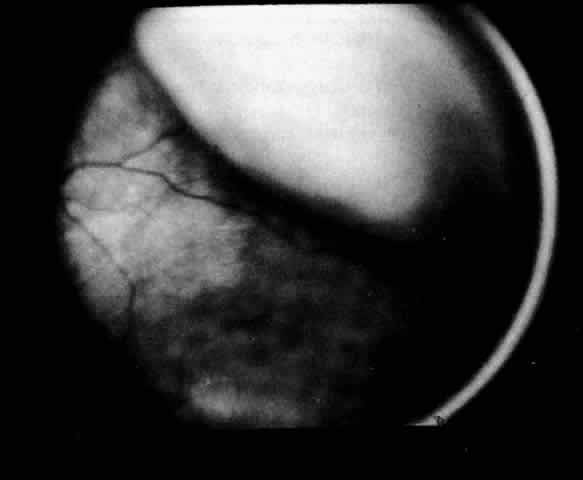

The presence of certain clinical characteristics may assist in the diagnosis of a ciliochoroidal effusion (Table 1). One clinical feature is choroidal edema. Choroidal edema may resemble a retinal detachment to a hasty observer; however, darkness of the uvea, lack of tremulousness, and normal retinal vessels indicate a probable uveal process (Fig. 1). The effusion may extend under the pars plana, allowing visualization of the ora serrata without scleral depression (Fig. 2).9 As shown in Figure 2, the surface of the elevation is convex and smooth, with a solid appearance and a homogeneous grayish color. A shallow anterior chamber and a low intraocular pressure may also suggest the diagnosis. Myopia in the presence of anterior displacement of the lens-iris diaphragm may be another diagnostic clue.10,11

Fig. 1. Painting of the ophthalmoscopic features of uveal effusion syndrome. There is a diffuse pigmentary disturbance in a dot, blot, or linear configuration and an annular ciliochoroidal effusion with secondary inferior retinal detachment.

Fig. 2. The ora serrata is visible in the pupillary space due to a ciliochoroidal effusion that developed after retinal detachment surgery in an aphakic eye. The arrow indicates the ora bay. (Courtesy of Retina Service, Wills Eye Hospital, Philadelphia)

Fig. 4. Clinical appearance of a lobular type of ciliochoroidal effusion.

Fig. 5. Flat ciliochoroidal effusion. The ora serrata is visible without scleral depression in a patient with Schepens-Brockhurst syndrome. The arrow indicates the ora bay.